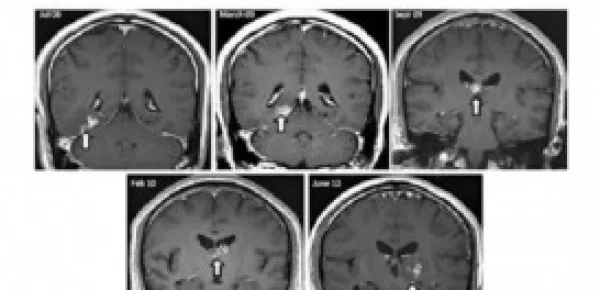

Il malcapitato è un cittadino britannico originario della Cina, che dal 2008 soffriva di questi fastidiosi disturbi, sino a quando ha deciso di rivolgersi ai medici i quali si sono accorti del parassita tramite alcune tac effettuate al cervello.

Il personale medico ha potuto constatare che la tenia si faceva largo tra le insenature del cervello, muovendosi indisturbata. Inizialmente avevano attribuito i sintomi ad alcune patologie come la sifilide, l'Hiv e la tubercolosi, ma poi successivamente, dopo approfonditi esami, si sono resi conto di avere a che fare con un animaletto che passeggiava nella calotta cranica del paziente.

Dopo aver effettuato due biopsie, hanno proceduto ad eseguire un intervento chirurgico per asportare l'intruso dal cervello dell'uomo. Il nome tecnico di questo essere è 'Spirometra erinaceieuropaei', un rarissimo parassita che può crescere sino ad un metro e mezzo di lunghezza e si trova generalmente nelle rane e nei crostacei.